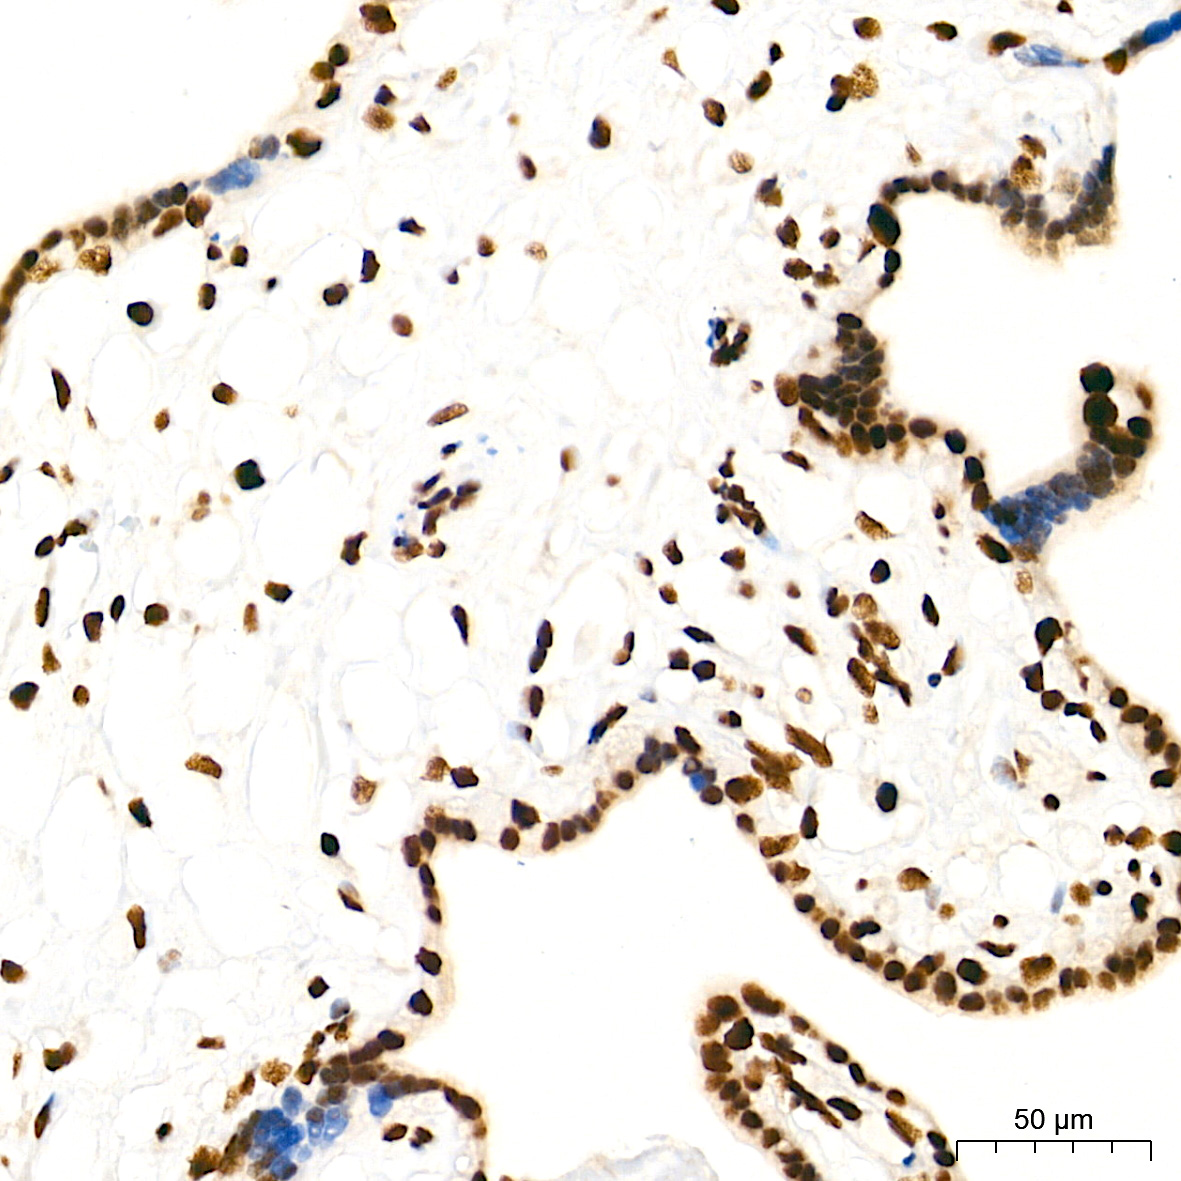

ABclonal基于第四代重组兔单抗SMab®技术平台,以ISO9001和ISO13485质量管理体系标准,为科研工作者研发并生产了一系列高特异性和高稳定性重组单克隆和多克隆抗体产品,这些抗体已针对多种应用进行了全面验证,用于神经谱系、神经退行性疾病(阿尔兹海默症、帕金森氏症、神经炎症)、神经发生、神经营养等神经生物学研究!